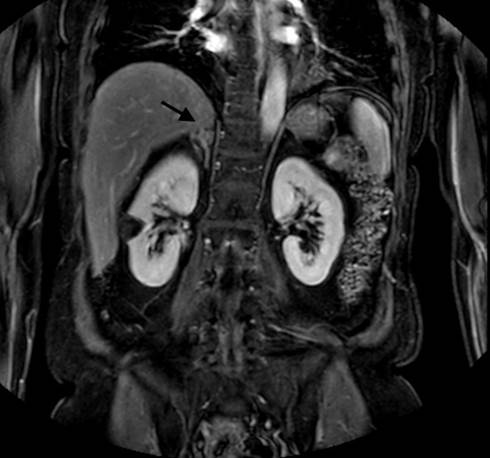

Laboratory workup reported a hemoglobin of 12 mg/dL (12-15.5 mg/dL), Urinalysis demonstrated microscopic hematuria with 10 rbc/hpf, and urinary metanephrines 0.3 (> 1.3 positive test). Magnetic Resonance (Figure 1 and 2) showed two ipsilateral renal tumors, one at the upper pole of 3.5 cm and the other at the mid-portion of the kidney of 3 cm, likewise an adrenal tumor of 1.5 cm was observed, normal chest x-ray.